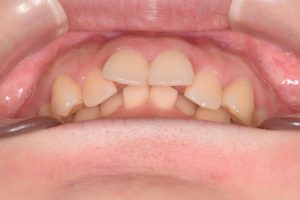

初診時(2022年9月)と装置撤去時(2025年9月)の写真です。

下から

0000000008

0000000136

・過蓋咬合

・叢生

・左右第二大臼歯シザーズバイト